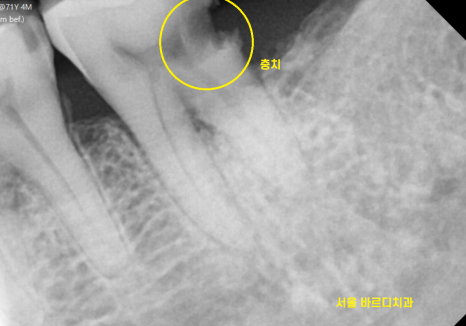

문제가 있어보이는 치아 2개

너무 아파서 발치를 원하셨습니다.

전남 완도 치과에서도

뽑아야한다 했는데

약을 먹고 버티고 계셨다 하셨습니다.

뿌리쪽 충치라 예후도 안좋고

염증으로 인하여 치아가 흔들려서

발치를 해야한다 환자분을 설득 드렸죠..